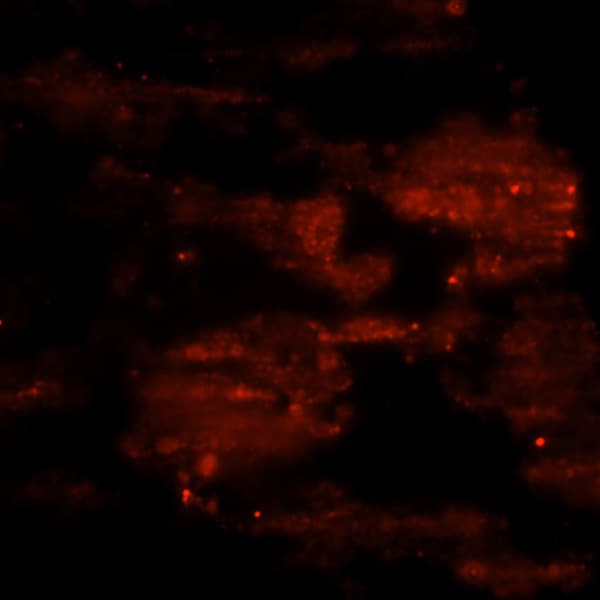

Intravital imaging of WT mouse liver showing movement of blood (FITC -dextran) through liver sinusoids.